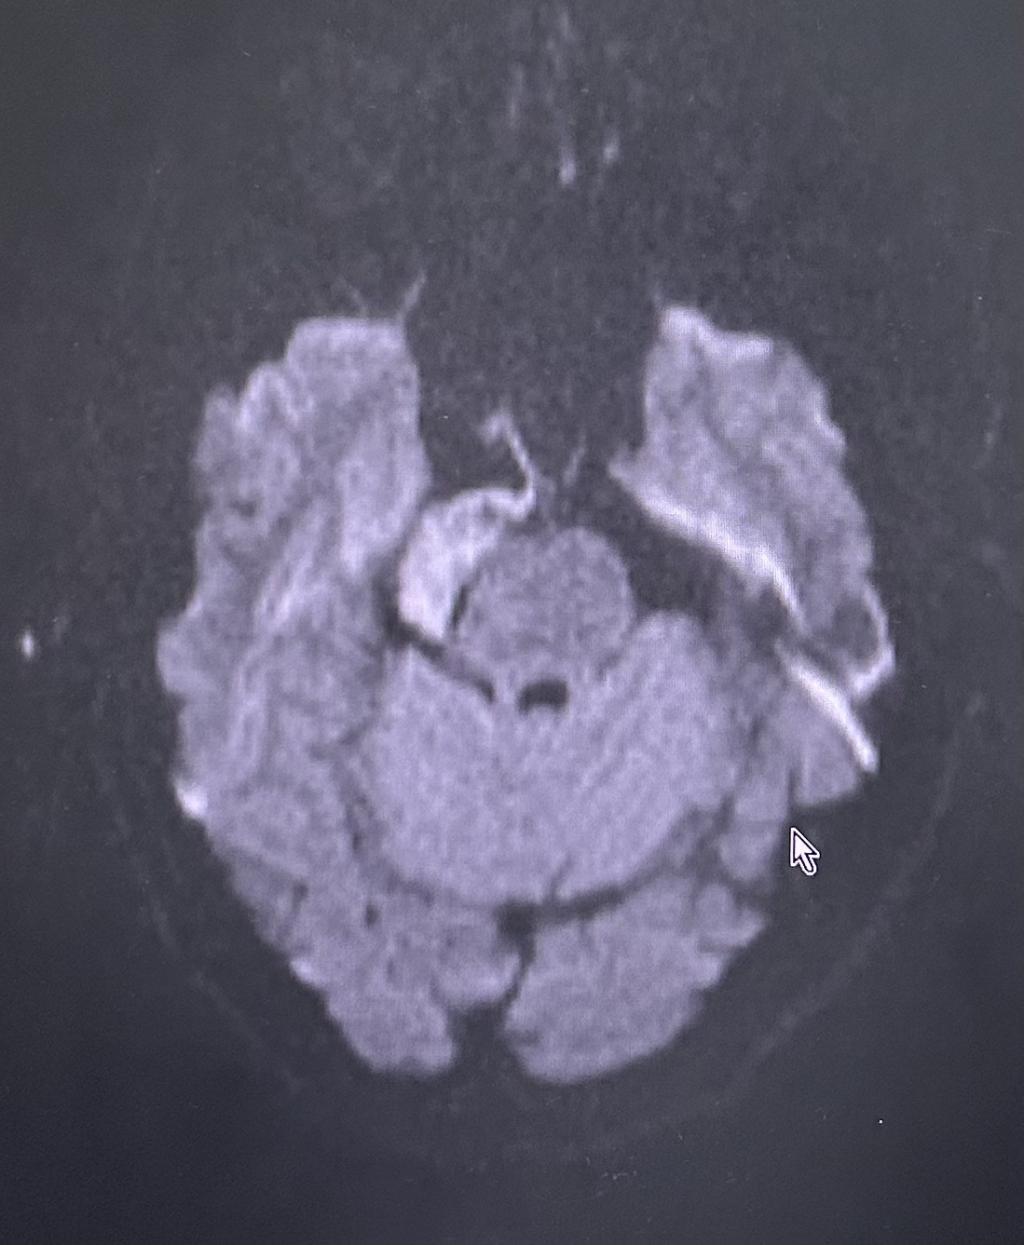

为求进一步治疗,贾女士慕名来到我院门诊就诊。门诊行颅神经-平扫(MR)提示:右侧桥小脑角区占位性病变,收治入神经外科住院治疗。

患者术前核磁共振影像